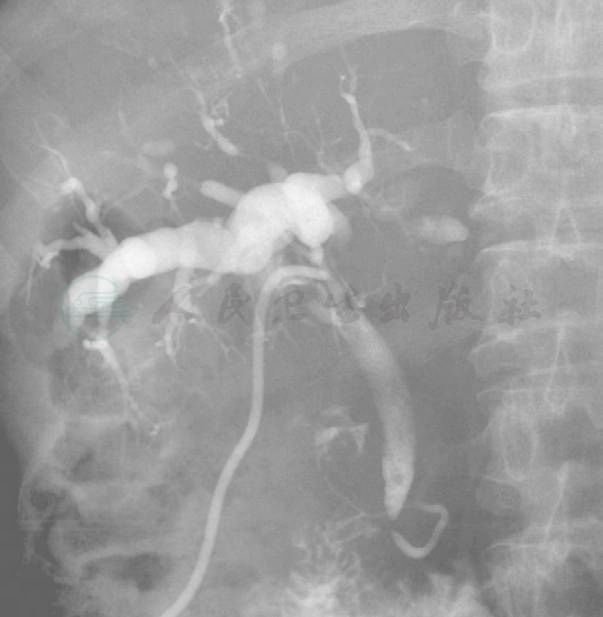

门诊行T形管造影:造影见肝内胆管显影,有扩张,呈藤蔓状改变,考虑和肿瘤侵犯有关,造影剂可顺利流入十二指肠(图2)。但在造影过程中,经T形管推注造影剂时阻力较大(使用碘海醇)。

图2 T形管造影情况